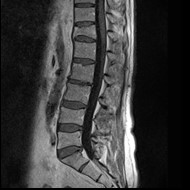

Na obrazie TK kręgosłupa strzałką wskazano wyrostek

A. poprzeczny.

B. kolczysty.

C. żebrowy.

D. stawowy.